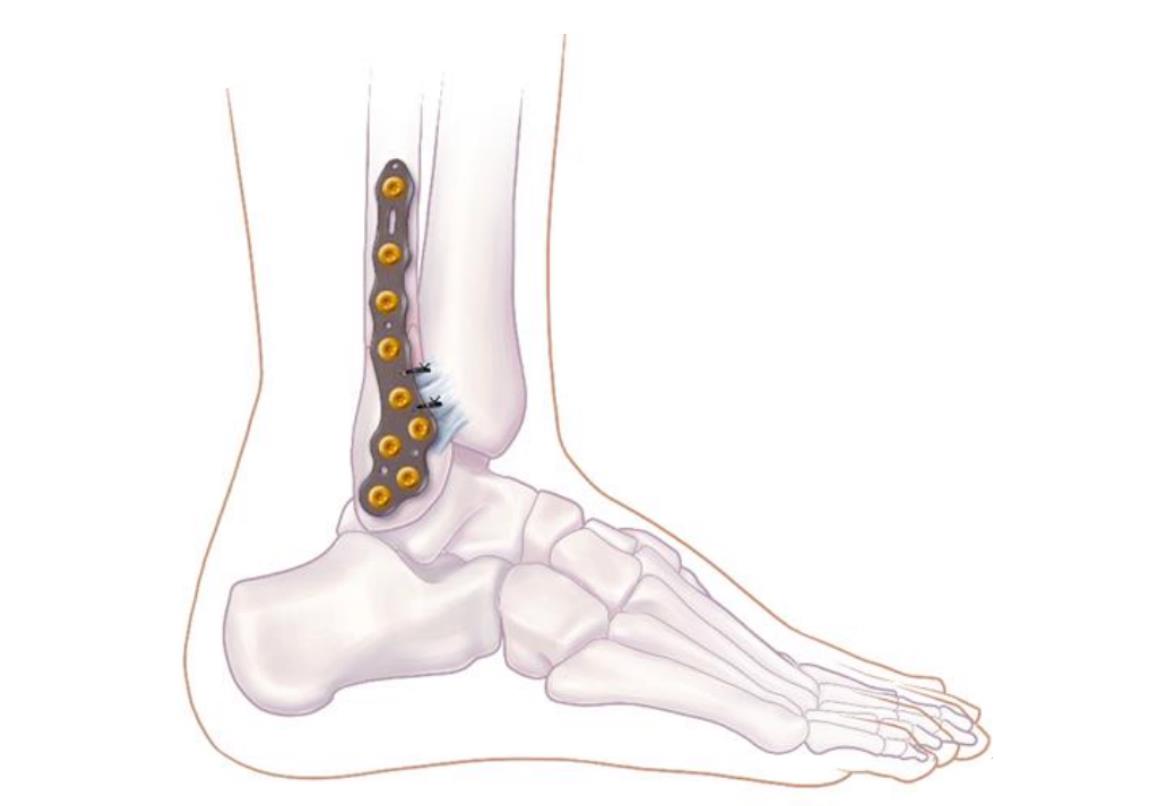

Volition® Ankle Fracture Plating

• VolitionTM Ankle Fracture Plates are available in six varieties: anatomic fibula plate, straight fibula plate, anatomic medial malleolar plate, posteromedial tibial plates (Type IIB), posterolateral tibial plates (Type IIA) and posterior tibial plates (Type III).

• lateral anatomical fibular plate